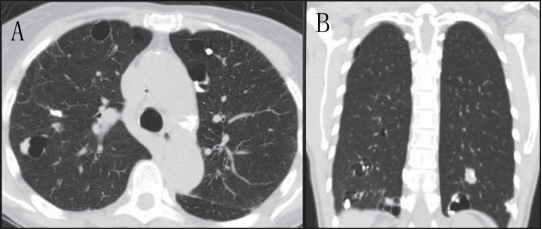

滤泡性细支气管炎(FB)也是累及肺的淋巴增生性疾病谱系的一种,与LIP主要区别为细支气管中心淋巴细胞浸润,不浸润到肺间质;此外,滤泡性毛细支气管炎最常见的表现形式是气道阻塞引起的空气潴留(11)。囊肿形成的主要机制是外部压迫支气管相关的淋巴组织,引起活瓣现象,但也可能与血管阻塞引起的细支气管缺血有关。这些囊肿与LIP囊肿相似,主要分布在支气管血管周围,薄壁(图4),也可以出现小叶中心结节或磨玻璃影。

4 女性滤泡细支气管炎患者的CT图像弥漫分布各种大小的薄壁囊肿,特别是沿支气管血管束周围的囊肿

5 A CT 轴位显示薄壁肺囊肿和右侧气胸。B, 冠状重建显示囊肿分布在下叶,以内侧为主。患者为49 岁女性,有突呼吸困难,被诊断为Birt-Hogg-Dube 综合症。